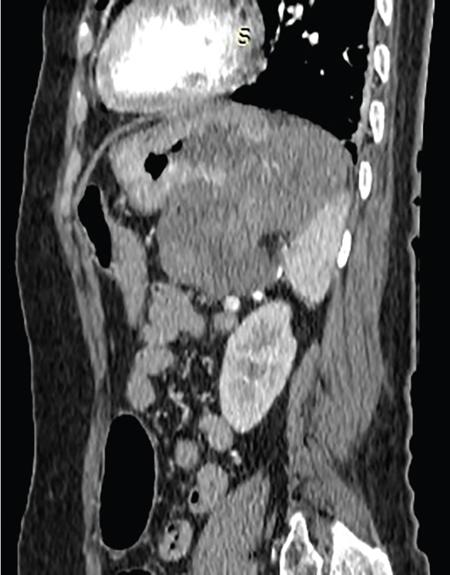

Single contrast barium study (Fig. 7.4.5.1), CECT (Figs. 7.4.5.2 and 7.4.5.3).

Fig 7.4.5.2 CECT of the patient.

Fig 7.4.5.3 CECT of the patient.

Observations

Barium study shows large filling defect in the antrum forming acute angles with the wall. Undulating contour is seen along greater curvature with ulceration of overlying mucosal irregularity.

CECT shows a large lobulated mass involving lesser curvature and antrum with marked wall thickening along distal greater curvature.

Diagnosis

Carcinoma stomach.